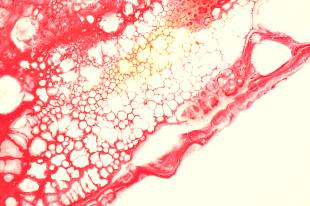

당뇨 전단계 증상은 혈액 속 포도당 농도가 정상 범위를 벗어나기 시작했지만 아직 당뇨병 진단선까지는 닿지 않은 경계 구간에서 나타날 수 있는 변화들입니다. 겉으로는 멀쩡해 보여도 몸속에서는 인슐린 작동이 둔해지고, 세포가 당을 받아들이는 문이 점점 뻑뻑해지는 일이 벌어집니다. 마치 도시의 물류창고 문이 잘 열리지 않아 길목에 짐이 쌓이듯, 혈당 조절의 흐름도 서서히 정체되기 시작합니다. 이 시기를 알아차리면 생활습관 교정만으로도 방향을 되돌릴 가능성이 충분히 있습니다.

당뇨병은 단순히 단것을 많이 먹어서 생기는 병으로만 볼 수 없으며, 유전적 소인, 복부비만, 활동량 부족, 수면 문제, 스트레스, 간의 대사 이상 같은 요소가 겹치며 진행되는 대사 질환입니다. 특히 전단계에서는 특별히 아픈 곳이 없어서 방심하기 쉽지만, 몸은 작은 신호를 여러 방향으로 흘려보냅니다. 조용한 파도처럼 밀려오는 변화들을 일찍 읽어내는 것이 중요하며, 건강검진의 수치와 생활 중 느끼는 감각을 함께 살피는 습관이 예방의 핵심이 됩니다.